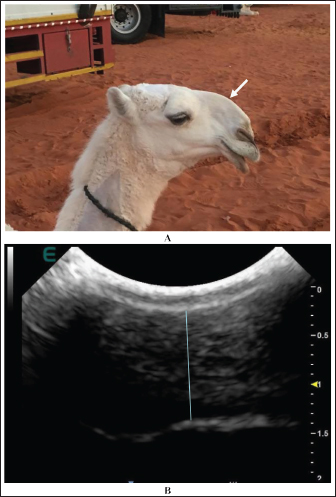

Extension and stretching of the lips in camels due to daily massage of the lips and sometimes binding with a rubber band resulted in blood congestion and lip enlargement (Fig. 7). Radiographic evaluation of filler materials in the perinasal region showed swelling of the soft tissues to the extent of variable degrees owing to the injected fillers; the injected substances appeared gray and had a soft tissue density (Fig. 8). In the injected lips, the injected filler was hypoechoic, and the scanning manner of the injected lips appeared heterogeneous (Fig. 9). In the perinasal area, the filler material appeared as either hypoechogenic or anechoic spots (Fig. 10). In infrared thermography (IRT), stretched lips appeared lighter and more heterogeneous than the darker and homogenous lips of healthy camels. In addition, the injected lip sites appeared darker than the surrounding tissue as their temperature was relatively higher when compared with healthy non-injected lip tissue (Fig. 11). Figure 12 shows a camel with enlargement of the lips due to filler injection, while Figure 13 shows enlargement of the soft palate or dulla and clitoris due to testosterone hormonal injection.

Fig. 10. Enlargement of the perinasal area in a female camel due to injection of filler material (white arrow) (A). Image (B) shows the ultrasonographic detection of the injected filler material (blue line) that appeared hypoechoic with anechoic spots.

Fig. 11. Injection points (1, 2, 3) of the lips in a female camel using filler material (a). Image (b) shows the detection of the three injected points by thermography.

Tampering is usually detected in camels either by close clinical examination, ultrasound examination, and thermography or by laboratory tests to estimate the level of hormones in the blood (Tharwat and Al-Hawas, 2021, 2023; Tharwat et al., 2021a, 2024a,b). In this study, ultrasonography was valuable for verifying the different cosmetic methods used by camels. The injected substance appeared of low echogenicity, and the scanning image of the injected lips showed heterogeneity with increasing overall lip thickness. In cases with lip binding, the tip of the lips appeared either isoechoic with a hypoechoic rim or hypoechoic with an echogenic center. This finding is in agreement with previously reported results (Tharwat and Al-Hawas, 2021). In the perinasal area, the filler material appeared as either hypoechoic or anechoic spots. These findings agree well with recently reported findings on human beings (Chai et al., 2022; Jiang et al., 2022). In this study, sonography was superior to radiography and thermography. Sonography was the easy, safe, and reliable methodology that was implemented in situ for a large number of examined camels to obtain quick and accurate results.